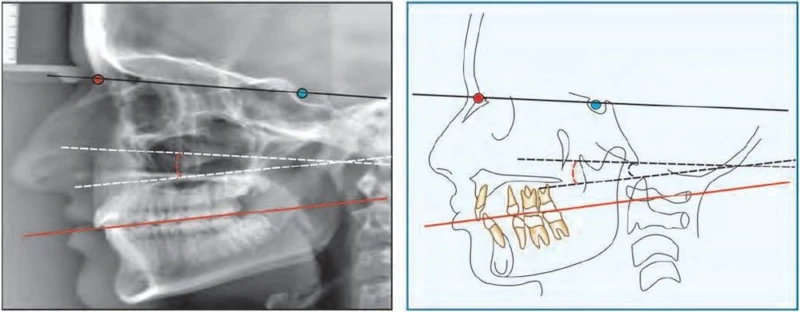

Tương quan xương hàm trên so với nền sọ

Góc SNA được tạo nên bằng cách nối các đường thẳng S-N và N-A. Giá trị trung bình của góc này là 82o. Nếu số đo góc này lớn hơn 82o có nghĩa là xương hàm trên nằm về phía trước hay nhô xương hàm trên. Ngược lại, nếu số đo góc này nhỏ hơn 82o nghĩa là xương hàm trên nằm về phía sau hoặc lùi xương hàm trên.

Tương quan giữa xương hàm dưới so với nền sọ

Để đánh giá liệu xương hàm dưới nhô hay lùi so với nền sọ thì cần đo góc SNB. Giá trị trung bình của góc này là 80o.

Nếu góc này nhỏ hơn 80o cho thấy xương hàm dưới lùi. Nếu góc này lớn hơn 80o cho thấy xương hàm dưới đi ra phía trước hay nhô xương hàm dưới.

Tương quan giữa xương hàm trên và xương hàm dưới

Góc ANB cung cấp thông tin về mối tương quan giữa vị trí xương hàm trên và xương hàm dưới. Góc ANB cho thấy sự bất cân xứng theo chiều trước sau của nền chóp xương hàm trên và xương hàm dưới.

Giá trị trung bình của góc này là 2 độ. Góc này lớn hơn 2 độ cho thấy khuynh hướng xương hạng II. Theo nguyên tắc, góc này càng lớn thì sự chênh lệch theo chiều trước sau của xương hàm càng lớn, và do đó việc sửa chữa sai khớp cắn càng khó khăn.

Góc này nhớ hơn 2 độ và có giá trị âm (chẳng hạn – 1 độ, -2 độ v.v…) cho thấy xương hàm dưới nằm về phía trước so với xương hàm trên, tương quan xương hạng III.